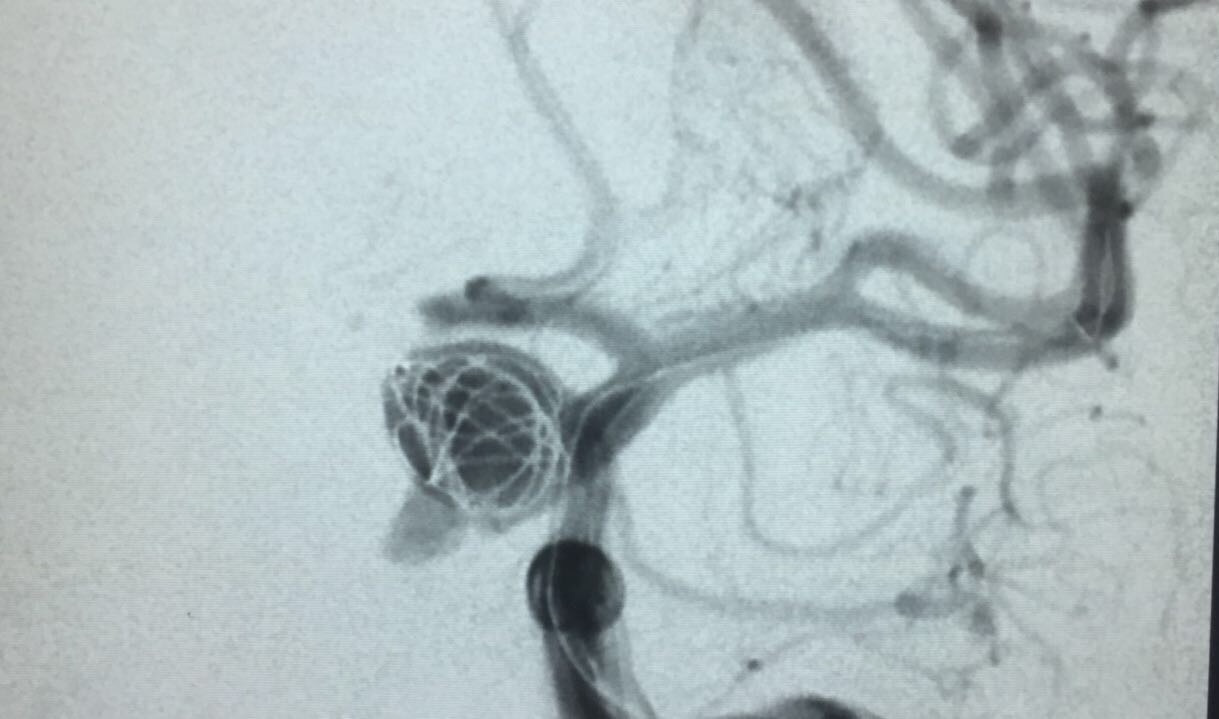

Paciente foi então encaminhada ao setor de hemodinâmica sendo realizado Angiografia cerebral Digital e evidenciado aneurisma de segmento oftálmico da artéria carótida interna esquerda. Realizado embolização do aneurisma com microespirais, sem intercorrências. A paciente permanece em bom estado geral e neurológico recuperando em pós operatório imediato.